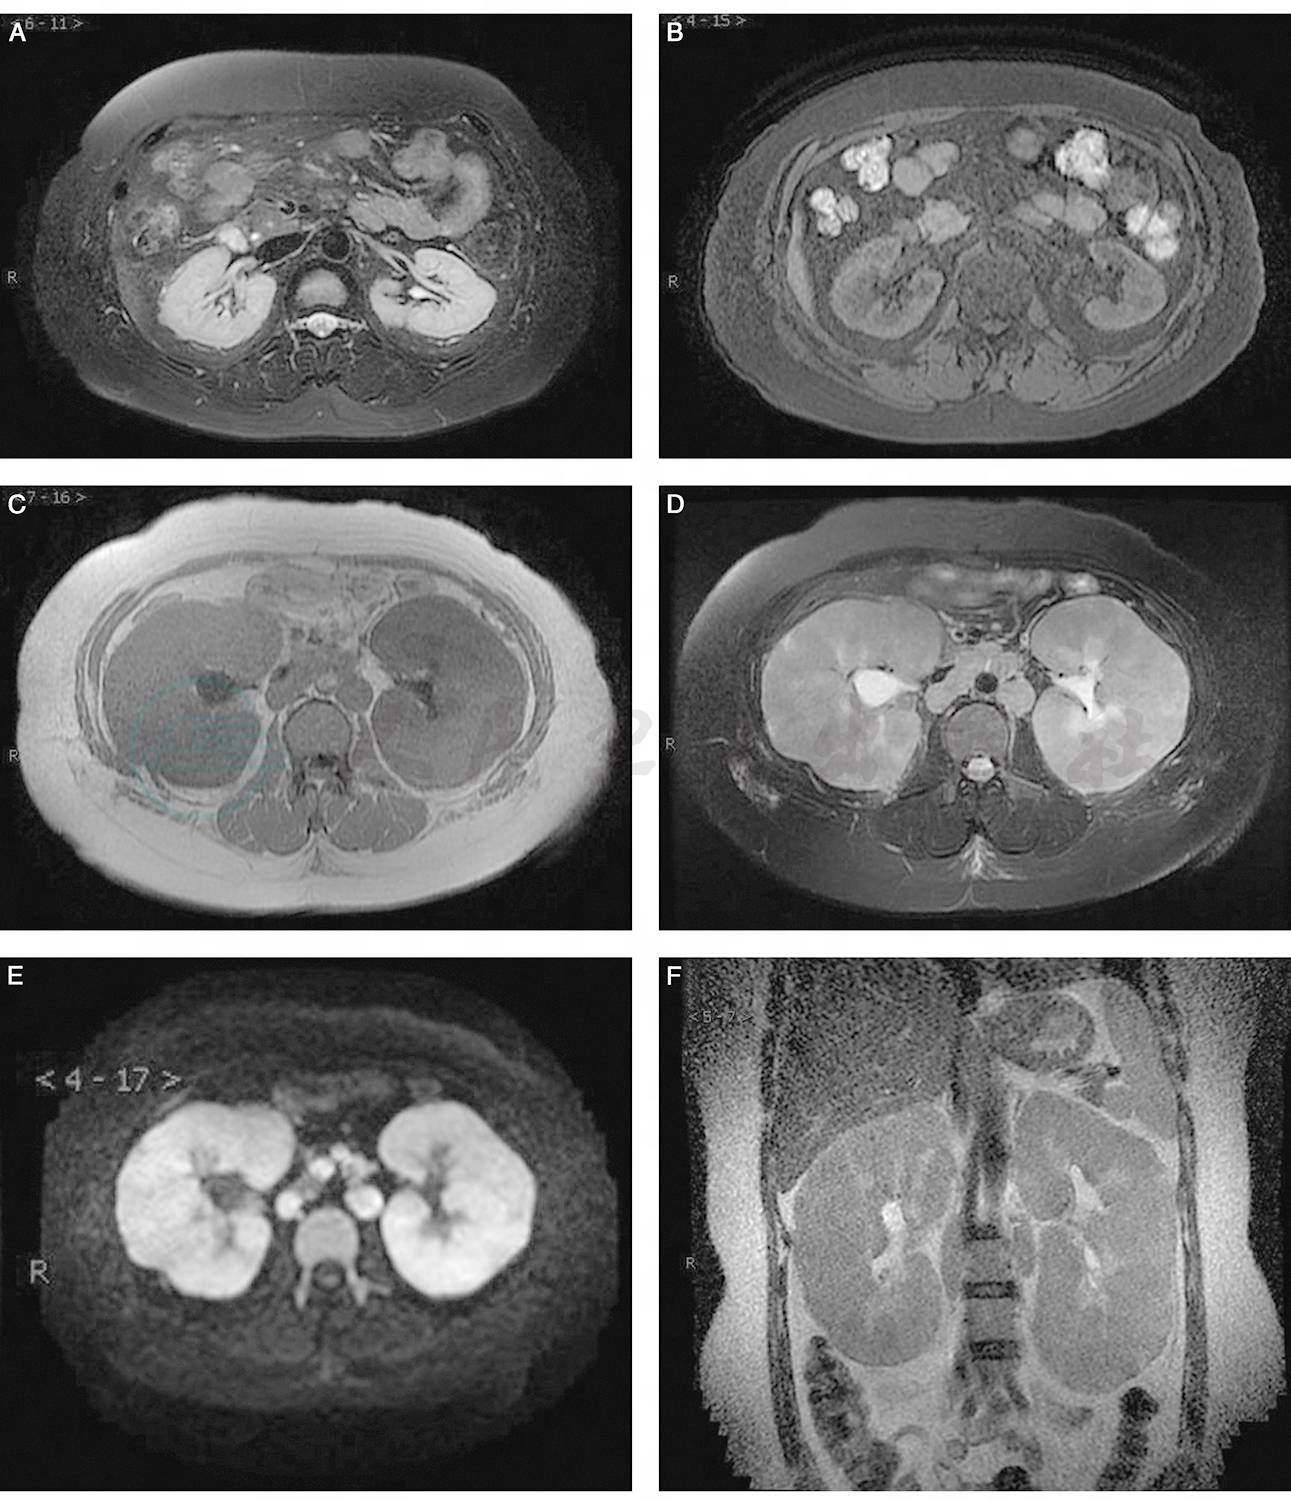

患者青年女性,急性病程,以急性肾损伤伴双肾异常增大为主要临床表现。尿检结果提示肾脏病变位于肾小管间质。常见的肾小管间质损伤的原因如自身免疫性疾病、药物因素、毒物的损伤等,患者缺乏相应的病史,辅助检查也不支持。结合双肾显著弥漫增大,考虑肿瘤的肾脏浸润。由于患者为青年患者,胸片、B超未发现实性占位,故实体肿瘤可能性小,进一步进行的腹部CT也未发现肿瘤证据。为排查血液系统肿瘤,行骨穿检查,骨髓细胞学检查:呈增生骨髓象,未见异常细胞。骨髓流式细胞学:未见明显异常增殖细胞群;骨髓活检未见明显异常。故考虑到淋巴瘤细胞浸润可能,需进行病理学检查。由于未发现其他脏器存在病变的证据,需行肾脏活检明确。但该患者肾脏异常肿大,进行肾活检存在肾脏破裂的风险,因此予甲泼尼龙40mg静脉滴注试验治疗及血液透析支持治疗,患者经激素治疗后体温正常,腰疼明显减轻,血压下降,一周后复查透前血清肌酐降为112μmol/L,复查肾脏长径较前缩小2cm。进一步腹部MRI显示(图1):双肾弥漫增大,多发结节,腹膜后多发肿大淋巴结,疑诊双肾淋巴瘤。进行肾脏穿刺活检,肾脏病理显示肾小球无明显病变;肾小管弥漫萎缩及消失;肾间质弥漫形态一致的淋巴细胞浸润,部分凋亡。免疫组化染色TdT(+++),PAX5(+++),Ki67(>90%阳性);CD3(-),CD34(-),CD20(-),考虑 B 淋巴母细胞淋巴瘤。术后未出现肾周血肿。

图1 肾脏MRI:双肾弥漫增大,多发结节,腹膜后多发肿大淋巴结